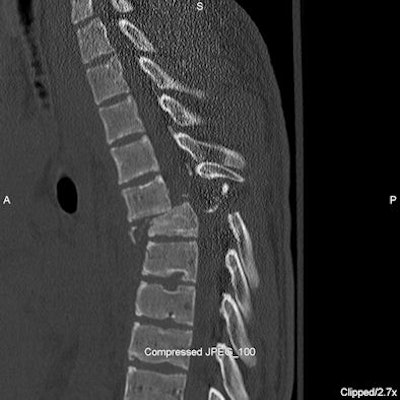

Twenty-one children had spinal fractures, and five children had spinal cord injuries.

| Spinal cord injury: Sagittal CT (above) and short-tau inversion recovery (STIR) MRI (below) images of the thoracic spine of a 16-year-old male who was found in a ditch by a passerby after a rollover ATV accident. He suffered compression fractures of T5 and T6 with anterior subluxation of T5 over T6 with intraspinal fracture fragments and severe spinal cord injury. Spinal cord showed near complete transaction at this level. Subsequently, he developed dural cerebrospinal fluid leak at T5-6 level. He also suffered fracture of C2 vertebra and multiple facial bone fractures. He was not wearing a helmet. On a recent follow-up eight months after the injury, there is no improvement in paraplegia. All images courtesy of Dr. Chetan Shah. |